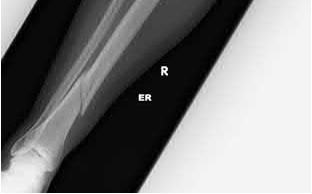

What is the most common type of malalignment after intramedullary nailing of distal 1/3 extra-articular tibia fractures using a infrapatellar approach when compared with plating?

The most common type of malalignment after intramedullary nailing of distal 1/3 extra-articular tibia fractures using an infrapatellar approach when compared with plating is valgus malalignment.

Fixation of distal one-third tibial shaft fractures can be successfully treated with either intramedullary nailing or plating. The literature describes advantages and disadvantages to both approaches, however intramedullary nailing has been shown to lead to increased rates of valgus malunion. Recent studies have shown that using a suprapatellar approach may decrease the incidence of valgus malalignement.

Vallier et al performed a randomized prospective study to compare plate and nail stabilization for distal tibia shaft fractures by assessing complications and secondary procedures. One-hundred and four patients were randomized to either reamed intramedullary nailing, or medial distal tibia plate fixation.

Primary angular malalignment was identified in 17 patients (16.3%). This included four patients treated with tibial plating (8.3%) and 13 patients treated with nails (23%, P = 0.02). Eight of these (7.7% of all patients) had malalignment between 6° and 10° of angulation. Valgus was the most common

angular deformity, accounting for 70% of angular deformity cases.

Avilucea et al. looked at the immediate postoperative alignment of distal tibia fractures (within 5 cm of the tibial plafond) treated with suprapatellar intramedullary nail (IMN) insertion compared with the infrapatellar technique. They found primary angular malalignment of ≥5 degrees occurred in 35 (26.1%) patients with infrapatellar IMN insertion and in 5 (3.8%) patients who underwent suprapatellar IMN insertion. They conclude suprapatellar IMN technique results in a significantly lower rate of malalignment compared with the infrapatellar IMN technique.